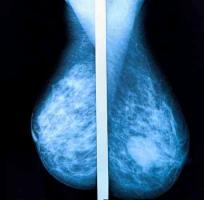

Invita IMSS Veracruz Norte a mujeres a campaña de mastografías

Con el propósito prevenir o, en su caso, detectar oportunamente el cáncer de mama, el Instituto Mexicano del Seguro Social (IMSS) en Veracruz Norte invita a las mujeres derechohabientes de 40 a 69 años, a acudir a la campaña de mastografías.

“Las mastografías buscan detectar cambios o anormalidades en los tejidos del seno que con el tiempo pueden dar problemas, si se descubre algún nódulo o masa, se deben realizar otros estudios para descartar o confirmar alguna otra patología”, explicó la coordinadora auxiliar médico de Salud Pública, doctor José Artemio Cruz López.